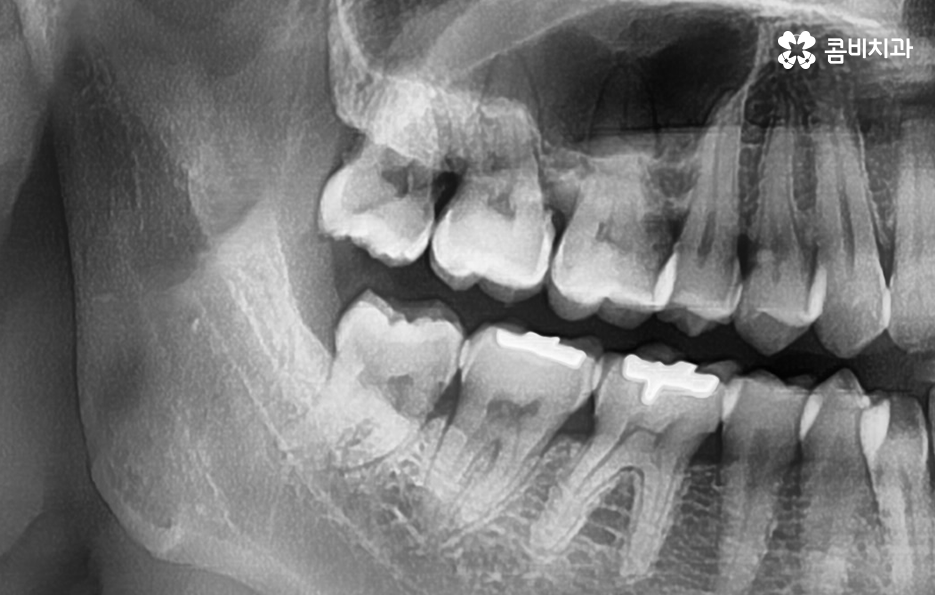

예를 들어 사랑니의 충치가 어금니의 인접면까지 같이 발생한 경우에는 사랑니 발치 만으로 끝나는 것이 아니라 어금니 치료까지 함께 진행되어야 하는 경우도 있고 사랑니로 인한 염증이 심해진 경우에도 잇몸 치료가 발치와 함께 진행되어야 하는 경우도 있을 거예요

사랑니를 쉽게 뽑기 위해서는 이러한 문제가 발생되기 전에 미리 인지하고 초기에 대처하는 것이 중요한데 사랑니의 발치 자체는 숙련된 치과 의사에 의해 진행되겠지만 사랑니는 발치 뿐 아니라 건강하게 잇몸이 회복되는 것까지 고려해야 하기 때문에 치료 시점이 중요할 수 있어요

과거에는 매복사랑니 발치를 위해 대학병원에 가야했던 경우도 많았지만 요즘은 대학병원에서 근무했던 경험이 있는 치과의사가 직접 치과를 개원한 경우도 많기 때문에 숙련된 치과의사를 잘 찾는다면 매복사랑니도 어렵지 않게 발치할 수 있는데요

일반적으로 상악보다는 하악이 하치조 신경과 턱뼈가 근접하기 때문에 좀더 세심한 발치를 해야하며 정상 맹출된 사랑니 보다는 완전 매복되어 있는 사랑니 발치가 고난도의 발치로 분류되고 있어요